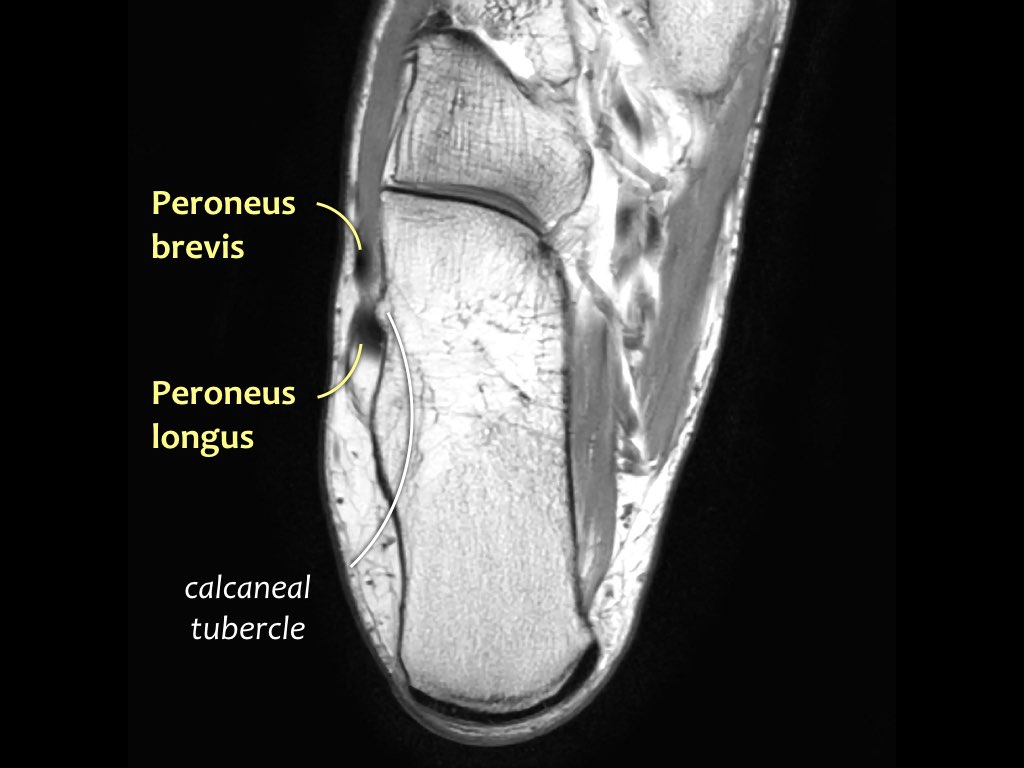

- Khoang ngoài

- Gân cơ mác dài (Peroneus Longus)

- Gân cơ mác ngắn (Peroneus Brevis)

Hướng đi của các gân dọc theo mắt cá trong và mắt cá ngoài có thể gây ra hiện tượng ‘xảo ảnh góc ma thuật’.

Các gân sẽ biểu hiện tín hiệu tăng tương đối khi tạo góc 55° so với B0, dễ nhầm lẫn với bệnh lý như viêm gân hoặc rách gân một phần.

Xảo ảnh này xuất hiện trên các chuỗi xung có thời gian TE ngắn (ví dụ: PD).

Trên các chuỗi xung có TE dài (như T2), xảo ảnh này cũng xuất hiện nhưng ít rõ rệt hơn.